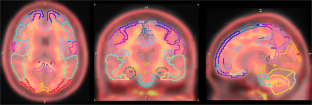

Cerebral Amyloid Quantification in Cognitively Normal Korean Adults Using F-18 Florbetaben PET

We prospectively analyzed F-18 FBB positron emission tomography (PET)/CT scans of 30 cognitively healthy adults (age range, 50–70 years) using automated quantification. The standardized uptake value ratios (SUVRs) of F-18 FBB were calculated for predefined regions by normalizing the regional count with cerebellar cortex.

The distribution of amyloid beta for each brain region revealed no age-related trends (p > 0.05). From all subjects, mean SUVR of amyloid deposit was 1.30 ± 0.18. The right parietal lobe showed the highest SUVR value (1.46 ± 0.23), whereas the right frontal lobe and left precuneus showed the lowest SUVR (1.23 ± 0.25).

Fig. 1

Fig. 2